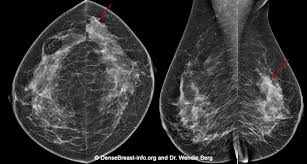

My bone mets were discovered during a bone scan (i.e. Should i be insisting on one even though my lymph nodes were clear? Combining a pet scan with an mri or ct scan can help make the images easier to interpret. This tracer can help identify areas of cancer that an mri or ct scan may not show. Lobular breast cancer can be more difficult to see on imaging and scans.

Cureus Excellent Response With Ado Trastuzumab Emtansine In A Patient With Relapsed Metastatic Breast Cancer Presenting With Pulmonary Lymphangitic Carcinomatosis from assets.cureus.com This helps radiologists identify areas where cells are suspiciously active, which can indicate cancer. Imaging and lobular breast cancer. This tracer can help identify areas of cancer that an mri or ct scan may not show. Areas of tumor tend to pick up the labeled compound and show up as foci of increased activity either bright or dark spots depending how the image is displayed. Finding breast lumps and seeing change in the size and shape. Lobular breast cancer can be more difficult to see on imaging and scans. (1) gary ulaner, md, phd, facnm. What does breast cancer look like?

Imaging and lobular breast cancer. When a breast cancer has been diagnosed, some people have a ct scan of their chest and tummy (abdomen) to stage the breast cancer. 4.9k views reviewed >2 years ago What does breast cancer look like? Your doctor and radiographer make sure the benefits of having the test outweigh these risks. Controversy continues to surround the question of whether ct and bone scans should be standard in evaluating patients for these metastases, or whether integrated pet/ct scanning might. To help you prepare, here's a look at what to expect. With cancer cells, they appear as bright spots due to its higher metabolic rate compared to normal cells. It is common for patients to receive a diagnosis for cancer of unknown primary. Ct scans can be misread or misinterpreted. The big problem with imaging is that we know, with certainty, that we can't usually. Combining a pet scan with an mri or ct scan can help make the images easier to interpret. As you probably know, a ct scan is one of several imaging techniques—this one primarily for looking at organs.

Small Cell Lung Cancer With Metastasis To The Breast A Case Report And Review Of The Literature from www.jscimedcentral.com Controversy continues to surround the question of whether ct and bone scans should be standard in evaluating patients for these metastases, or whether integrated pet/ct scanning might. Breast mri is most often used to screen for breast cancer in women thought to have a high risk of the disease. Identify the correct area for. Imaging tests usually can't tell if a change has been caused by cancer. As you probably know, a ct scan is one of several imaging techniques—this one primarily for looking at organs. Your doctor may recommend a breast mri scan if you have a diagnosis of breast cancer to determine the extent of the cancer. I have my yearly check up in a few weeks time. A patient undergoing a breast ct scan will lie face down on a table that is slid into a scanner that takes photographs of the patient's chest area.